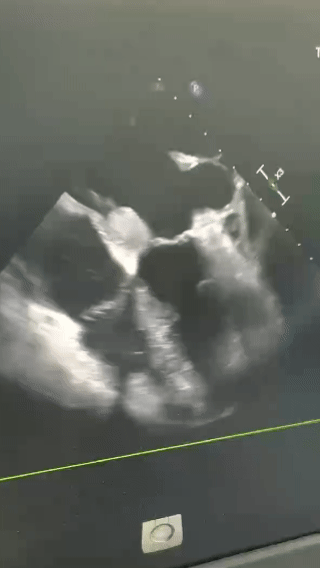

从去年9月份开始,徐女士察觉到自己总是活动后胸闷气喘,年后这些症状较之前越来越严重,来到我院检查后才发现她的左心房内竟长了一颗约65mm×40mm的巨大肿瘤!瘤体在左心房与左心室中来回甩动,随时可能脱落或者堵塞二尖瓣口,存在猝死风险!更棘手的是,她还合并高血压、糖尿病、中度肺动脉高压等多种基础疾病,身体异常羸弱,手术难度和风险远超常规!

3月7日,在北京安贞医院安徽医院心脏外科龚文辉专家团队指导下,医院专家团队为徐女士实施了“心脏肿瘤切除术 + 二尖瓣成形术 + 三尖瓣成形术”这一高难度四级手术。术中,专家们精准剥离、完整切除65mm×40mm的巨大胶冻状肿瘤,并对病变的二尖瓣、三尖瓣进行成形修复,成功解除了瓣膜反流问题,解除了猝死风险、改善了徐女士心脏功能!